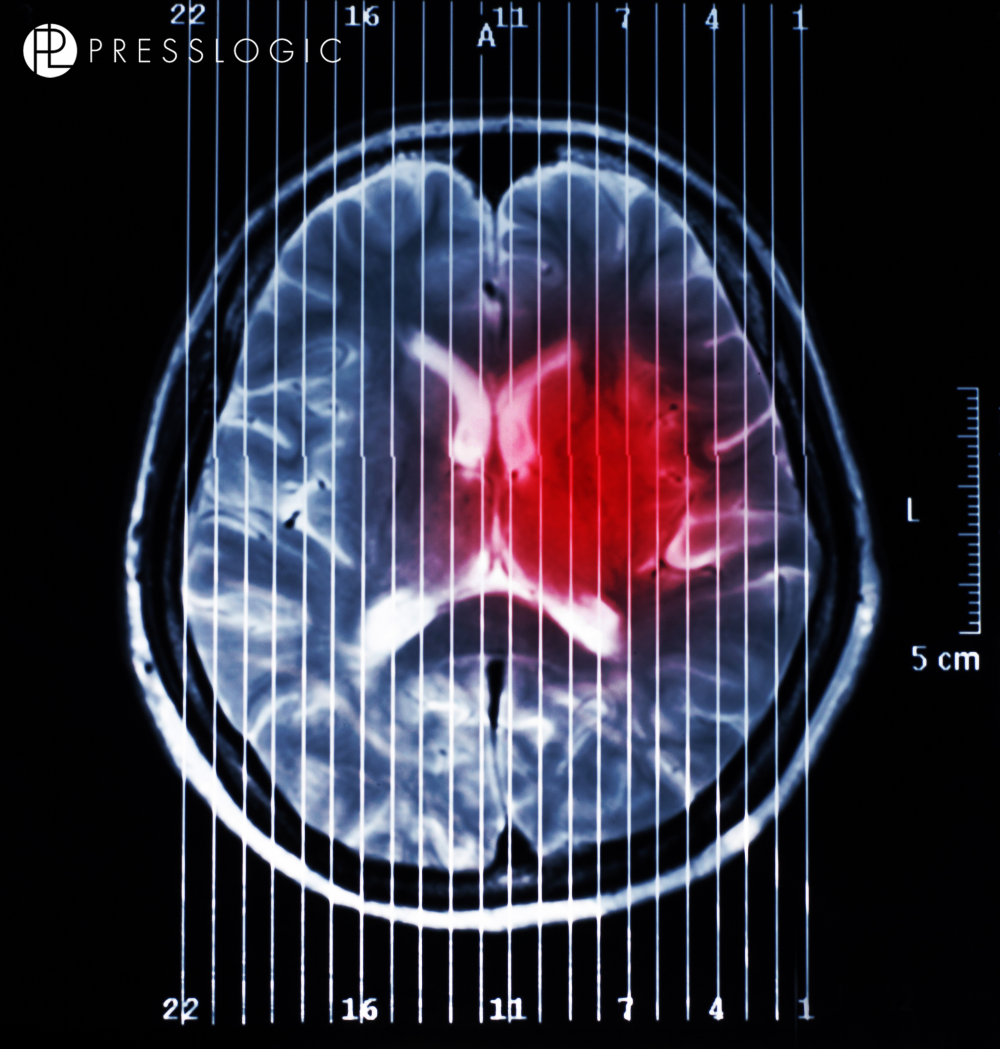

在許多不同類型的腦癌之中, 膠質母細胞瘤是成年人最常見的和最難治療的腦癌之一。它們能快速地生長和擴散,意味它們在大腦擴散後,令人很難看到腫瘤在哪裡結束,健康組織在哪裡。放射治療、化療和手術都可能不足以去除這些侵襲性癌症。雖然這些方法能殺死大部分腫瘤細胞,但會遺留少量膠質母細胞瘤幹細胞,這些幹細胞會繼續分裂,導致癌症復發。

不過,最近來自美國華盛頓大學醫學院和加州大學聖地亞哥分校的研究發現,寨卡病毒可以選擇性地感染和殺死成人大腦中難以治療的癌細胞。

研究人員周二在《實驗醫學雜誌》上發表論文稱,為驗證寨卡病毒的這種能力是否有助於活體動物腦癌的治療,研究人員進行了小鼠實驗。他們分別將病毒和安慰劑(鹽水)直接注射到癌症小鼠的腦腫瘤中。兩週後檢測顯示,注射病毒的小鼠腫瘤明顯小於注射安慰劑的小鼠,後續研究則表明,它們比後者活得更長。

研究人員將寨卡病毒注射入完全長大的老鼠後,令侵襲性腫瘤萎縮,而其他腦細胞則無損傷。與常規治療手段結合,或可提高此類癌症患者的生存機率。